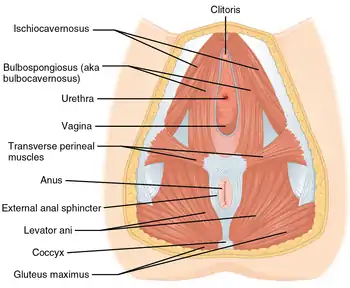

Pelvic floor muscles help to support the vulvar structures. The voluntary, pubococcygeus muscle, part of the levator ani muscle partially constricts the vaginal opening.[19] Other muscles of the urogenital triangle support the vulvar area and they include the transverse perineal muscles, the bulbospongiosus, and the ischiocavernosus muscles.[20] The bulbospongiosus muscle decreases the vaginal opening.[9] Their contractions play a role in the vaginal contractions of orgasm by causing the vestibular bulbs to contract.[21]

Blood, lymph and nerve supply

The tissues of the vulva are highly vascularised and blood supply is provided by the three pudendal arteries.[22] Venous return is via the external and internal pudendal veins.[23] The organs and tissues of the vulva are drained by a chain of superficial inguinal lymph nodes located along the blood vessels.[24]

The ilioinguinal nerve originates from the first lumbar nerve and gives branches that include the anterior labial nerves which supply the skin of the mons pubis and the labia majora.[25] The perineal nerve is one of the terminal branches of the pudendal nerve and this branches into the posterior labial nerves to supply the labia.[25] The pudendal nerve branches include the dorsal nerve of clitoris which gives sensation to the clitoris.[25] The clitoral glans is seen to be populated by a large number of small nerves, a number that decreases as the tissue changes towards the urethra.[26] The density of nerves at the glans indicates that it is the center of heightened sensation.[26] Cavernous nerves from the uterovaginal plexus supply the erectile tissue of the clitoris.[27] These are joined underneath the pubic arch by the dorsal nerve of the clitoris.[28] The pudendal nerve enters the pelvis through the lesser sciatic foramen and continues medial to the internal pudendal artery. The point where the nerve circles the ischial spine is the location where a pudendal block of local anesthetic can be administered to inhibit sensation to the vulva.[29] A number of smaller nerves split off from the pudendal nerve. The deep branch of the perineal nerve supplies the muscles of the perineum and a branch of this supplies the bulb of the vestibule.[30][31]